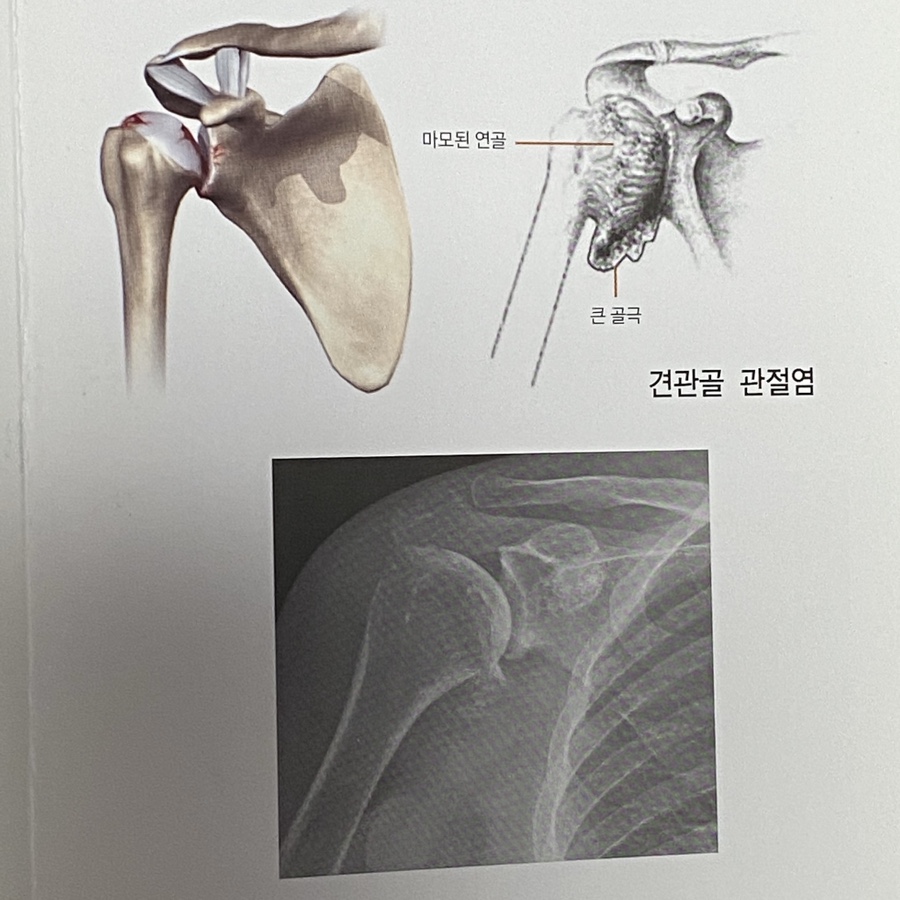

2. 퇴행성관절염

고관절 슬관벌에 비해 어깨관절은 체중부하를

하지 않는 관절이기에 상대적으로 드물지만,

한국인의 16퍼센트 정도에서 발생한다고 합니다.

3.류마티스 관절염

전신적인 관절 파괴의 진행이 특징적인

전신적 자가면역질환입니다.

류마티스관절염환자의 90퍼센트 이상에서

어깨 관절에 문제를 보이는 것으로 알려졌습니다.